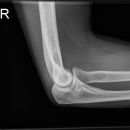

Ellenbogen seitlich nach N. Stjepanovic

Qualitätskriterien

Durch diese exakte Einstellung von N. Stjepanovic ist das humero-ulnar-Gelenk sehr gut einsehbar.